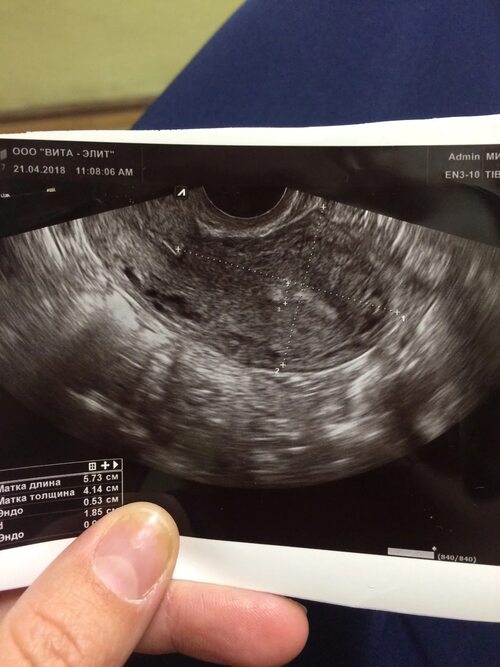

При УЗИ изображение плацентарного полипа может варьироваться в зависимости от его размера и местоположения. На снимках можно видеть ярко-отражающую структуру, прилегающую к стенке матки.

Фотографии плацентарного полипа на УЗИ могут быть полезны для визуального представления данной патологии. Они помогают лучше понять, как выглядит полип и как его можно отличить от других образований или нормальных структур в матке.